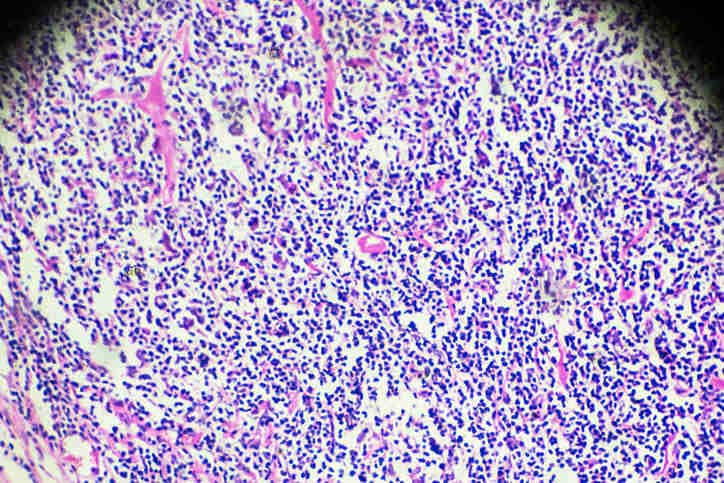

Immagine istopatologica del linfoma, al microscopio (iStock.com/jxfzsy)

Il patologo userà poi il microscopio per controllare se nel tessuto sono presenti cellule tumorali. Nel campione dei pazienti malati di solito sono presenti cellule anomale, di dimensioni maggiori del normale, dette cellule di Reed-Sternberg, che non si trovano nei tessuti delle persone sane.